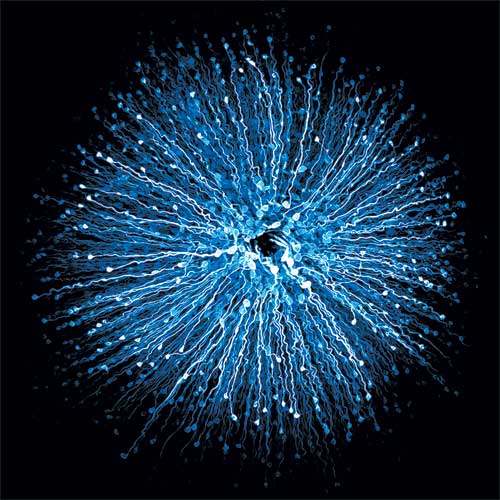

La thérapie optogénétique repose sur l’expression de protéines photosensibles généralement issues d’algues pour restaurer une sensibilité à la lumière de la rétine des patients aveugles. Cette stratégie fut introduite à l’Institut de la Vision dans un partenariat de Serge Picaud et du Pr Sahel avec le Dr Botond Roska de l’Institut d’ophtalmologie de Bâle (Suisse). Le Pr Sahel fit venir le Dr Jens Duebel (Chercheur CNRS) de l’Institut de Bâle et Deniz Dalkara (Directrice de Recherche Inserm) depuis l’université de Berkeley, spécialiste des vecteurs de thérapie génique pour développer cette approche prometteuse pour rendre la vision aux personnes aveugles. Le principe de l'optogénétique consiste à modifier génétiquement par thérapie génique les cellules résiduelles de la rétine afin de les rendre à nouveau sensibles par la lumière par la protéine d’algues. Après des essais concluants sur des tissus humains, des rongeurs et des primates non-humains, les premiers essais cliniques ont commencé avec des patients atteints de rétinopathie pigmentaire à l’hôpital de la vision des Quinze-Vingts sous la direction de la Pr Isabelle Audo, du Dr Elise Boulanger-Scemama et en partenariat avec l’entreprise, Gensight Biologics. La sensibilité de cette protéine étant plus faible que celle de nos photorécepteurs naturels, les chercheurs ont dû développer un dispositif intelligent de capture d’image combiné à une stimulation à forte luminance. Les patients doivent ainsi porter ces lunettes dotées de caméra pour augmenter l'intensité lumineuse des images. Certains patients aveugles atteints de rétinopathie pigmentaire ont ainsi retrouvé partiellement la vue grâce à la protéine d’algues. La poursuite de l’évaluation fonctionnelle des patients permettra de définir l'acuité visuelle procurée par cette nouvelle forme de thérapie.

Visualisation au microscope d'une fovéa, la partie centrale de la rétine. La fovéa est la région de l'œil responsable de l'acuité visuelle, nous permettant de lire, conduire ou encore reconnaître des visages. © Institut de la Vision